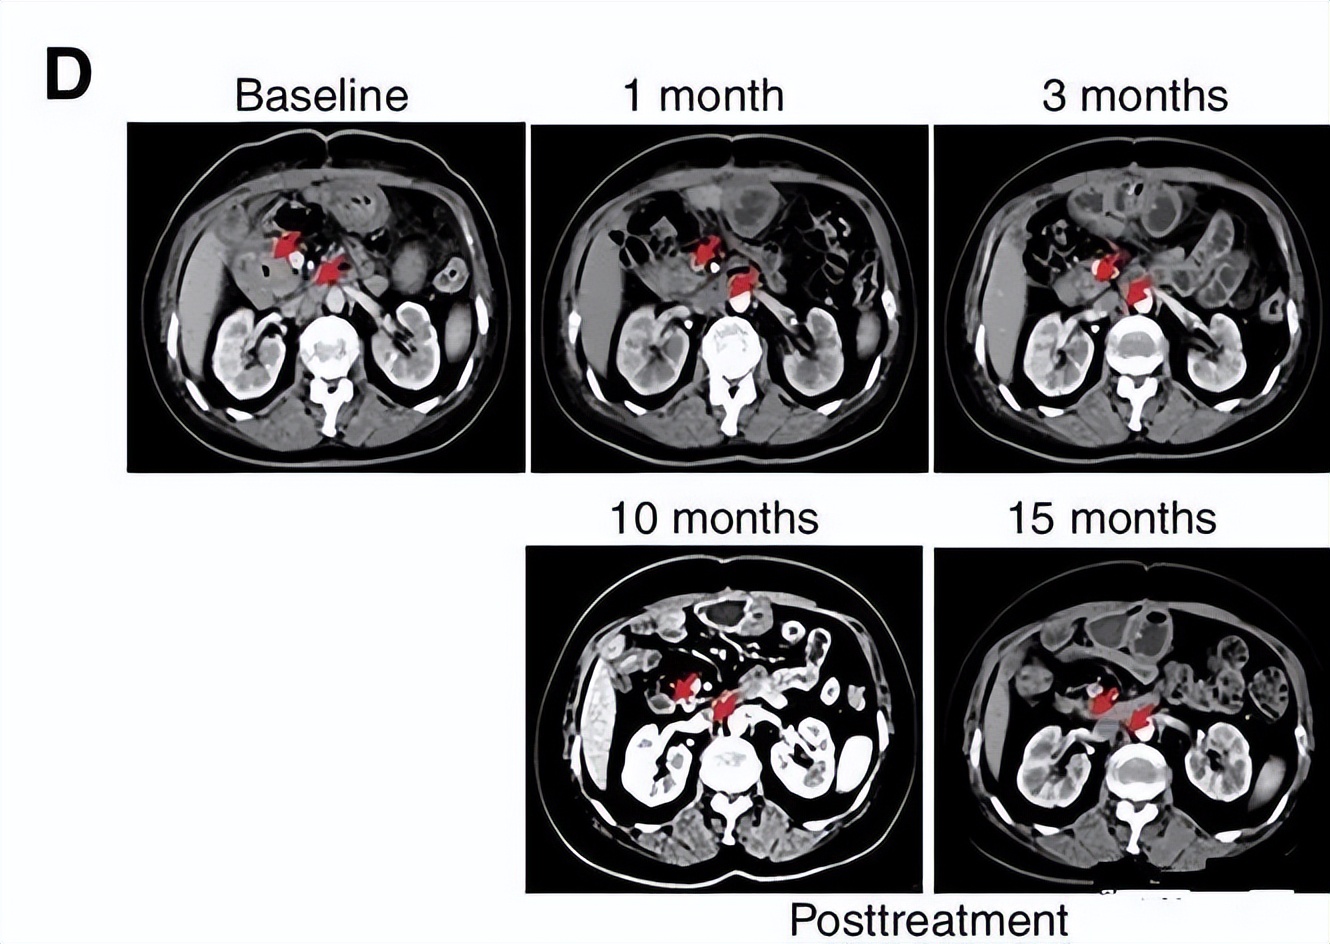

免疫疗法抗肿瘤效果图,央视新闻报道免疫细胞治疗癌症

△CART-RGFR细胞治疗之前和1、3、10和15个月患者1的CT扫描图像

这是中国团队自主研发的针对实体瘤的CAR-T第一次报道不错的临床疗效。极度恶性的胆管癌患者,首次出现了完全缓解。